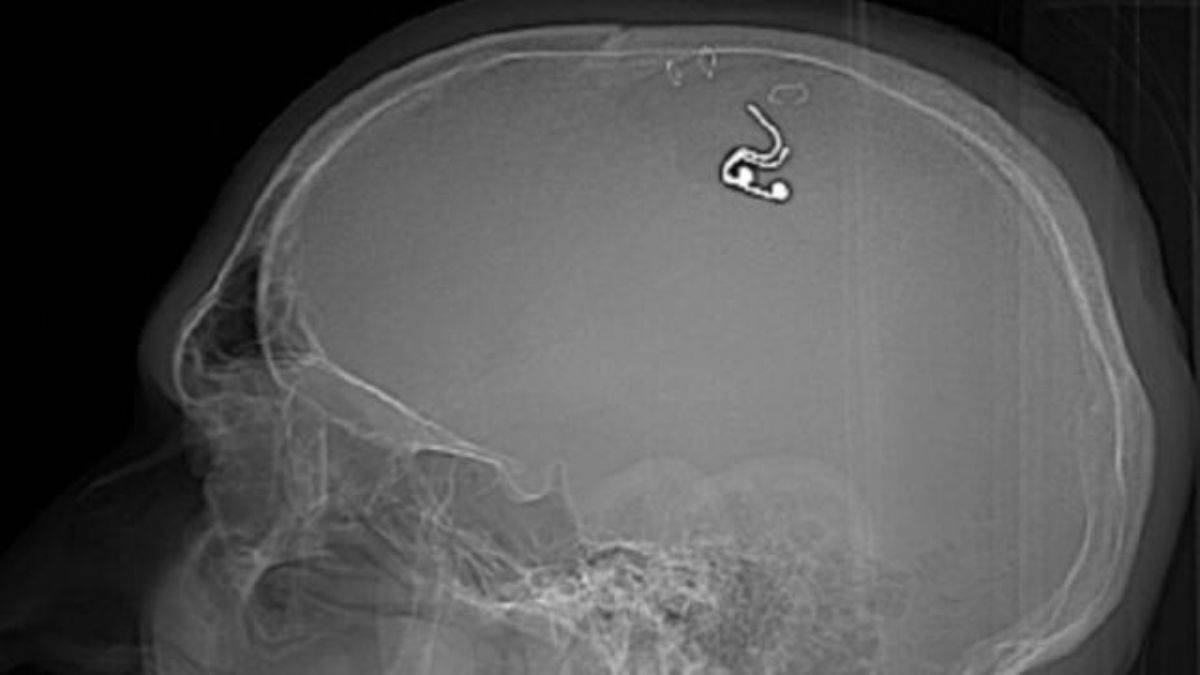

Rusya'da bir adam, rüyalarını kontrol etme amacıyla mikroçip takmak için kafatasını hırdavatçıdan aldığı matkapla deldikten sonra hastaneye kaldırıldı.

Michael Raduga isimli Rus uyruklu adam, kafasına ev tipi bir matkap kullanarak rüyalarını kontrol etmesine izin verecek bir çip yerleştirdi.

Telegram gönderisinde, "Bir matkap aldım, kafamda bir delik açtım ve beynime bir elektrot yerleştirdim" dedi.

Raduga ayrıca görüntüleri Twitter sayfasında paylaştı ve ameliyatı sırasında kan kaybından neredeyse ölüyor olmasına rağmen, sonuçların "gelecekteki rüya kontrol teknolojileri için harika umutlar" açtığını söyledi.